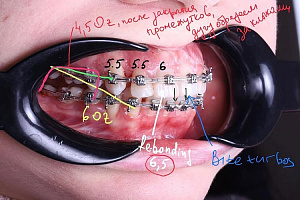

Гегиров Амир Артурович (@amir__ortodont)

Врач-ортодонт

#repost от @amir__ortodont

Была проведена полная фиксация брекетов на обе челюсти, установлены дуги и дополнительные элементы для запуска контролируемого перемещения зубов. Уже с первых месяцев лечения начинается работа над выравниванием зубных рядов, подготовкой места для правильного положения клыков и коррекцией прикуса.

В данном случае наблюдается выраженный дефицит места для клыков, поэтому лечение будет проходить поэтапно и с использованием дополнительной опоры. Каждый элемент системы работает на прогнозируемый и максимально эффективный результат.

Была проведена полная фиксация брекетов на обе челюсти, установлены дуги и дополнительные элементы для запуска контролируемого перемещения зубов. Уже с первых месяцев лечения начинается работа над выравниванием зубных рядов, подготовкой места для правильного положения клыков и коррекцией прикуса.

В данном случае наблюдается выраженный дефицит места для клыков, поэтому лечение будет проходить поэтапно и с использованием дополнительной опоры. Каждый элемент системы работает на прогнозируемый и максимально эффективный результат.